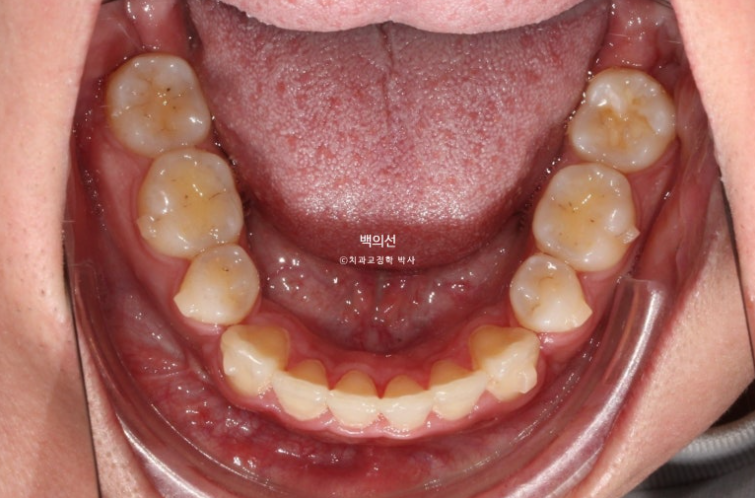

돌출입 수술을 하면 수술 테크닉적으로 작은어금니가 있던 공간이 약 2mm 이상이 남게 됩니다.

송곳니 뒤쪽에 2mm 의 공간이 각각 남았습니다.

이렇게 애매하게 남은 공간을 앞니 배열을 위한 공간으로 사용하는 것이 돌출입 수술교정의 핵심입니다.

이 정도의 남은 공간은 14개의 장치 안에서 해결 가능하기에 인비절라인 라이트로 충분합니다.